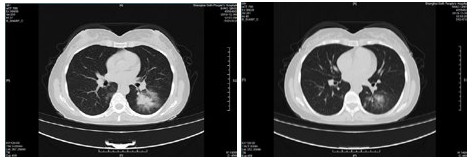

| 图 4 患者,男性,59岁,湖北籍,春节回乡探亲返沪,发热2 d入院,体温37.8℃, 乏力,既往体健。血白细胞总数及淋巴计数正常,甲型、乙型流感筛查阴性,新型冠状病毒核酸检测阳性。肺部CT提示双肺多发磨玻璃结节,病灶贴近胸膜伴支气管充气征及血管充血、增粗,可见部分纤维条索影 Fig 4 Case 4, male, 59 years old, born in Hubei Province, returned to Shanghai during the Spring Festival. He was hospitalized 2 days after fever, with a body temperature of 37.8℃ with fatigue. Normal WBC and lymphoid count, negative influenza A and B virus screening, positive novel coronavirus nucleic acid test. Lung CT showed multiple ground glass nodules in both lungs. The focus was close to the pleura, accompanied by bronchiectasis, hyperemia and thickening of blood vessels. Some fibrous bands could be seen |

| 图 5 患者,女性,44岁,沪籍,发病前10 d内有与确诊NCP患者接触史。出现发热,体温38.5℃,乏力,伴肌肉酸痛,既往体健。血白细胞总数及淋巴计数正常,甲型、乙型流感筛查阴性,新型冠状病毒核酸检测阳性。肺部CT提示双肺多发磨玻璃结节,病灶贴近胸膜伴支气管充气征及病变内血管充血、增粗 Fig 5 Case 5, female, 44 years old, born in Shanghai, had contact history with NCP patients within 10 days before the onset of the disease. Her body temperature was 38.5℃, with fatigue, muscle ache, previous physical fitness. Normal WBC and lymphoid count, negative influenza A and B virus screening, and positive novel coronavirus nucleic acid test. Lung CT showed multiple ground glass nodules in both lungs. The lesions were close to the pleura with bronchiectasis and congestion and thickening of blood vessels in the lesions |